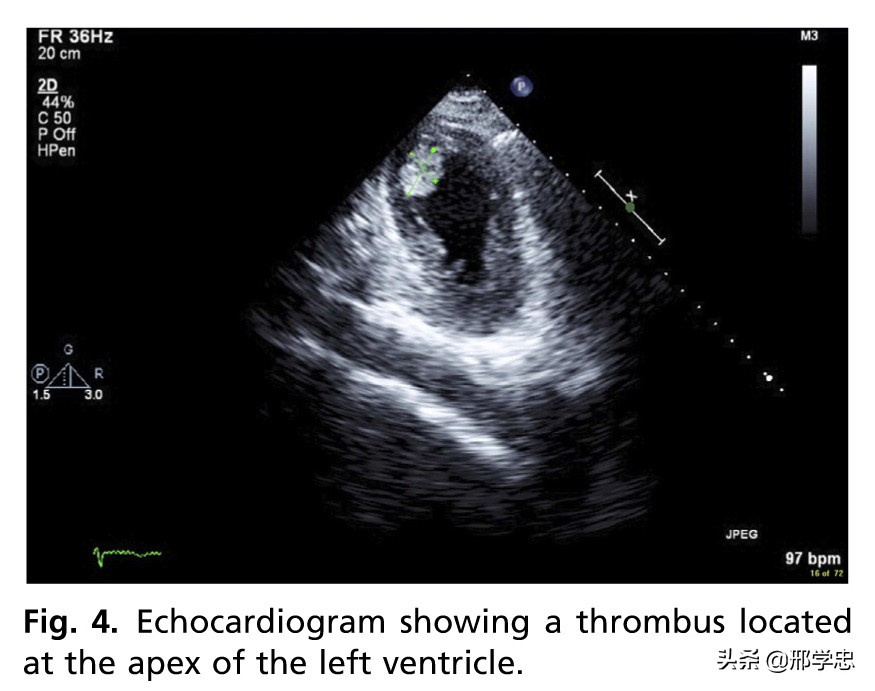

报道SIC患者心室血栓的发生率2.5%-8.0%,可以导致全身性栓塞或肺栓塞(图4)。

栓塞可以在病变的任何时期出现。左室壁运动异常以及LVEF下降可能是主要原因,但最近研究发现凝血异常可能促进SIC患者的栓塞。患者应该接受长期抗凝,影像学随访有助于监测心室血栓的缓解。

在德国意大利应激性心肌病登记研究中,541例SIC患者的2.2%(12例)出现左室血栓,患者均为女性,表现为心尖膨大样。所有患者均接受了口服抗凝治疗,但是2例患者在治疗开始前出现了脑血管事件。TnT水平增高是左室血栓的独立预测因素。长期随访发现,有无血栓对生存无影响。

经胸心动超声是评估可疑SIC患者的一线无创治疗。经胸心动超声联合多普勒超声可以快速评价急性期的左室功能异常(图1),还可以发现潜在的并发症无左室流出道梗阻(图3)和室性血栓(图4)等。这些信息对于患者的成功处理、风险评价和康复的监测是十分关键的。